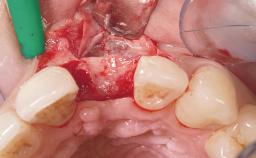

Immediate Placement of an Implant in a Maxillary Left Central Incisor Site

A 33-year-old female patient presented with an upper left central incisor that required extraction after a failed endodontic therapy. The tooth had been traumatized when the patient was a teenager and had undergone several endodontic treatments, including two apicectomy procedures. The patient was in good health and did not smoke. Clinical examination showed that the patient had a high lip line. In full smile, the gingival margins of the upper teeth were visible to the first molars. The gingival margins of central incisors 11 and 21 were only just showing. Examination of tooth 21 confirmed that the tooth was mobile and had hypererupted by 1 mm.

Bone Augmentation Horizontal|Simultaneous

Augmentation Materials Xenogenous|Membrane

Soft Tissue Grafting Simultaneous

Socket Integrity Damage to one or more bone walls

Bone Volume Damage to one or more socket walls